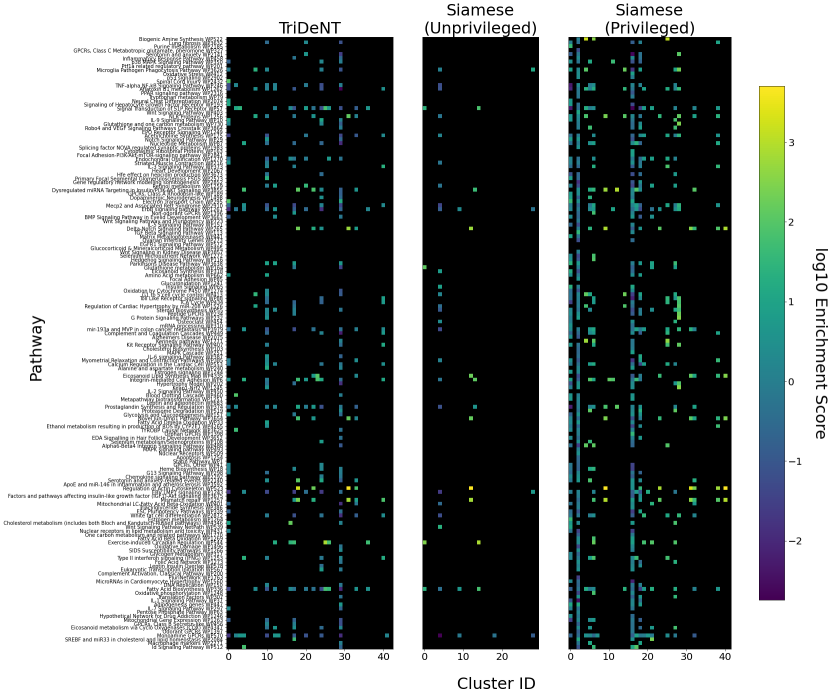

To assess the level of information shared between the transcriptomic results and the representations of the H&E patches, we investigate the cross-correlation between elements of the representations and the gene counts for each matching patch. We calculate the cross-correlation across the validation set between each element in the representations and the count for each gene, and for each gene take the correlation of the corresponding element with the maximum correlation or minimum anti-correlation, whichever has the greater absolute value. This maximum/minimum is chosen because the vast majority of elements will not correlate with any given gene, and the absolute value is taken because the sign of the element is arbitrary, so correlation and anti-correlation are equivalent. We use the absolute value of the correlation for the element selected for each gene, and use these to generate the histograms in Figure 3(a). It is clear that privileged training obtains representations which are far more correlated to the gene counts than unprivileged training, with minimal differences in the correlations between TriDeNT ♆ and Siamese approaches. This implies that the models have learned equivalently informative representations about the coarse-grained features of the genes. Figure 3(c) demonstrates that the correlation strength is significantly greater for TriDeNT ♆ compared to an unprivileged Siamese model, and Figures S3 and S4 show the relationships between the gene correlations of representations from TriDeNT ♆, Siamese methods, and supervised learning. Figures S5 and S6 show the geneset enrichment for each method, demonstrating that TriDeNT ♆ captures more meaninful interrelationships that are more informative about the relationship between tissue morphology and gene expression than unsupervised Siamese models. This is especially important for scientific discovery, as these analyses are used to generate hypotheses for further research. Figure S7 shows UMAP projections of the representation space coloured by genotype and gene, to illustrate that TriDeNT ♆ identifies distinct morphological clusters which are not found by unprivileged Siamese models. Figure 3(a) also shows that the findings are robust to human and mouse datasets, indicating the generality of the method.

To further analyse the learned representations, we produce UMAP projections of the latent space labelled with the tissue types for the NCT tissue type classification task, as shown for CD3CD20 and SMA in Figure 4(a), and for all SegPath stains in Figures S8 and S9. These figures make the reasons for the varying performance of the privileged Siamese model more apparent. For stains with better performing privileged Siamese models, such as SMA, the UMAPs are very similar between Siamese methods and TriDeNT, with well-differentiated tissue type clusters. In those with worse performance, such as ERG, the tissue types are poorly differentiated, often with only adipose and background forming distinct clusters from the other classes. On closer inspection, it is notable in these projections that TriDeNT ♆ produces more well-defined and separated clusters in general than Siamese networks. This is further evidenced in Figure S7, where TriDeNT ♆ is shown to identify clusters with overexpression of a given gene significantly more effectively than an unprivileged Siamese model.

The utility of TriDeNT ♆ for research applications can be found not only in increasing the efficacy of primary data models for prediction accuracy, but also in training models to extract coarse-grained features which are relevant to the privileged input. A typical use case is that a scientist with a paired dataset could train a model to then evaluate an unpaired dataset, without needing to acquire more paired data. We have shown that the features which are found by privileged methods are significantly different from those found by unprivileged methods. This means that TriDeNT ♆ could enable the identification of novel morphological clusters that are functionally important, such as those in our analyses in Figures 4(a) and S7, which might not emerge from other methods of training or training on the new dataset alone.